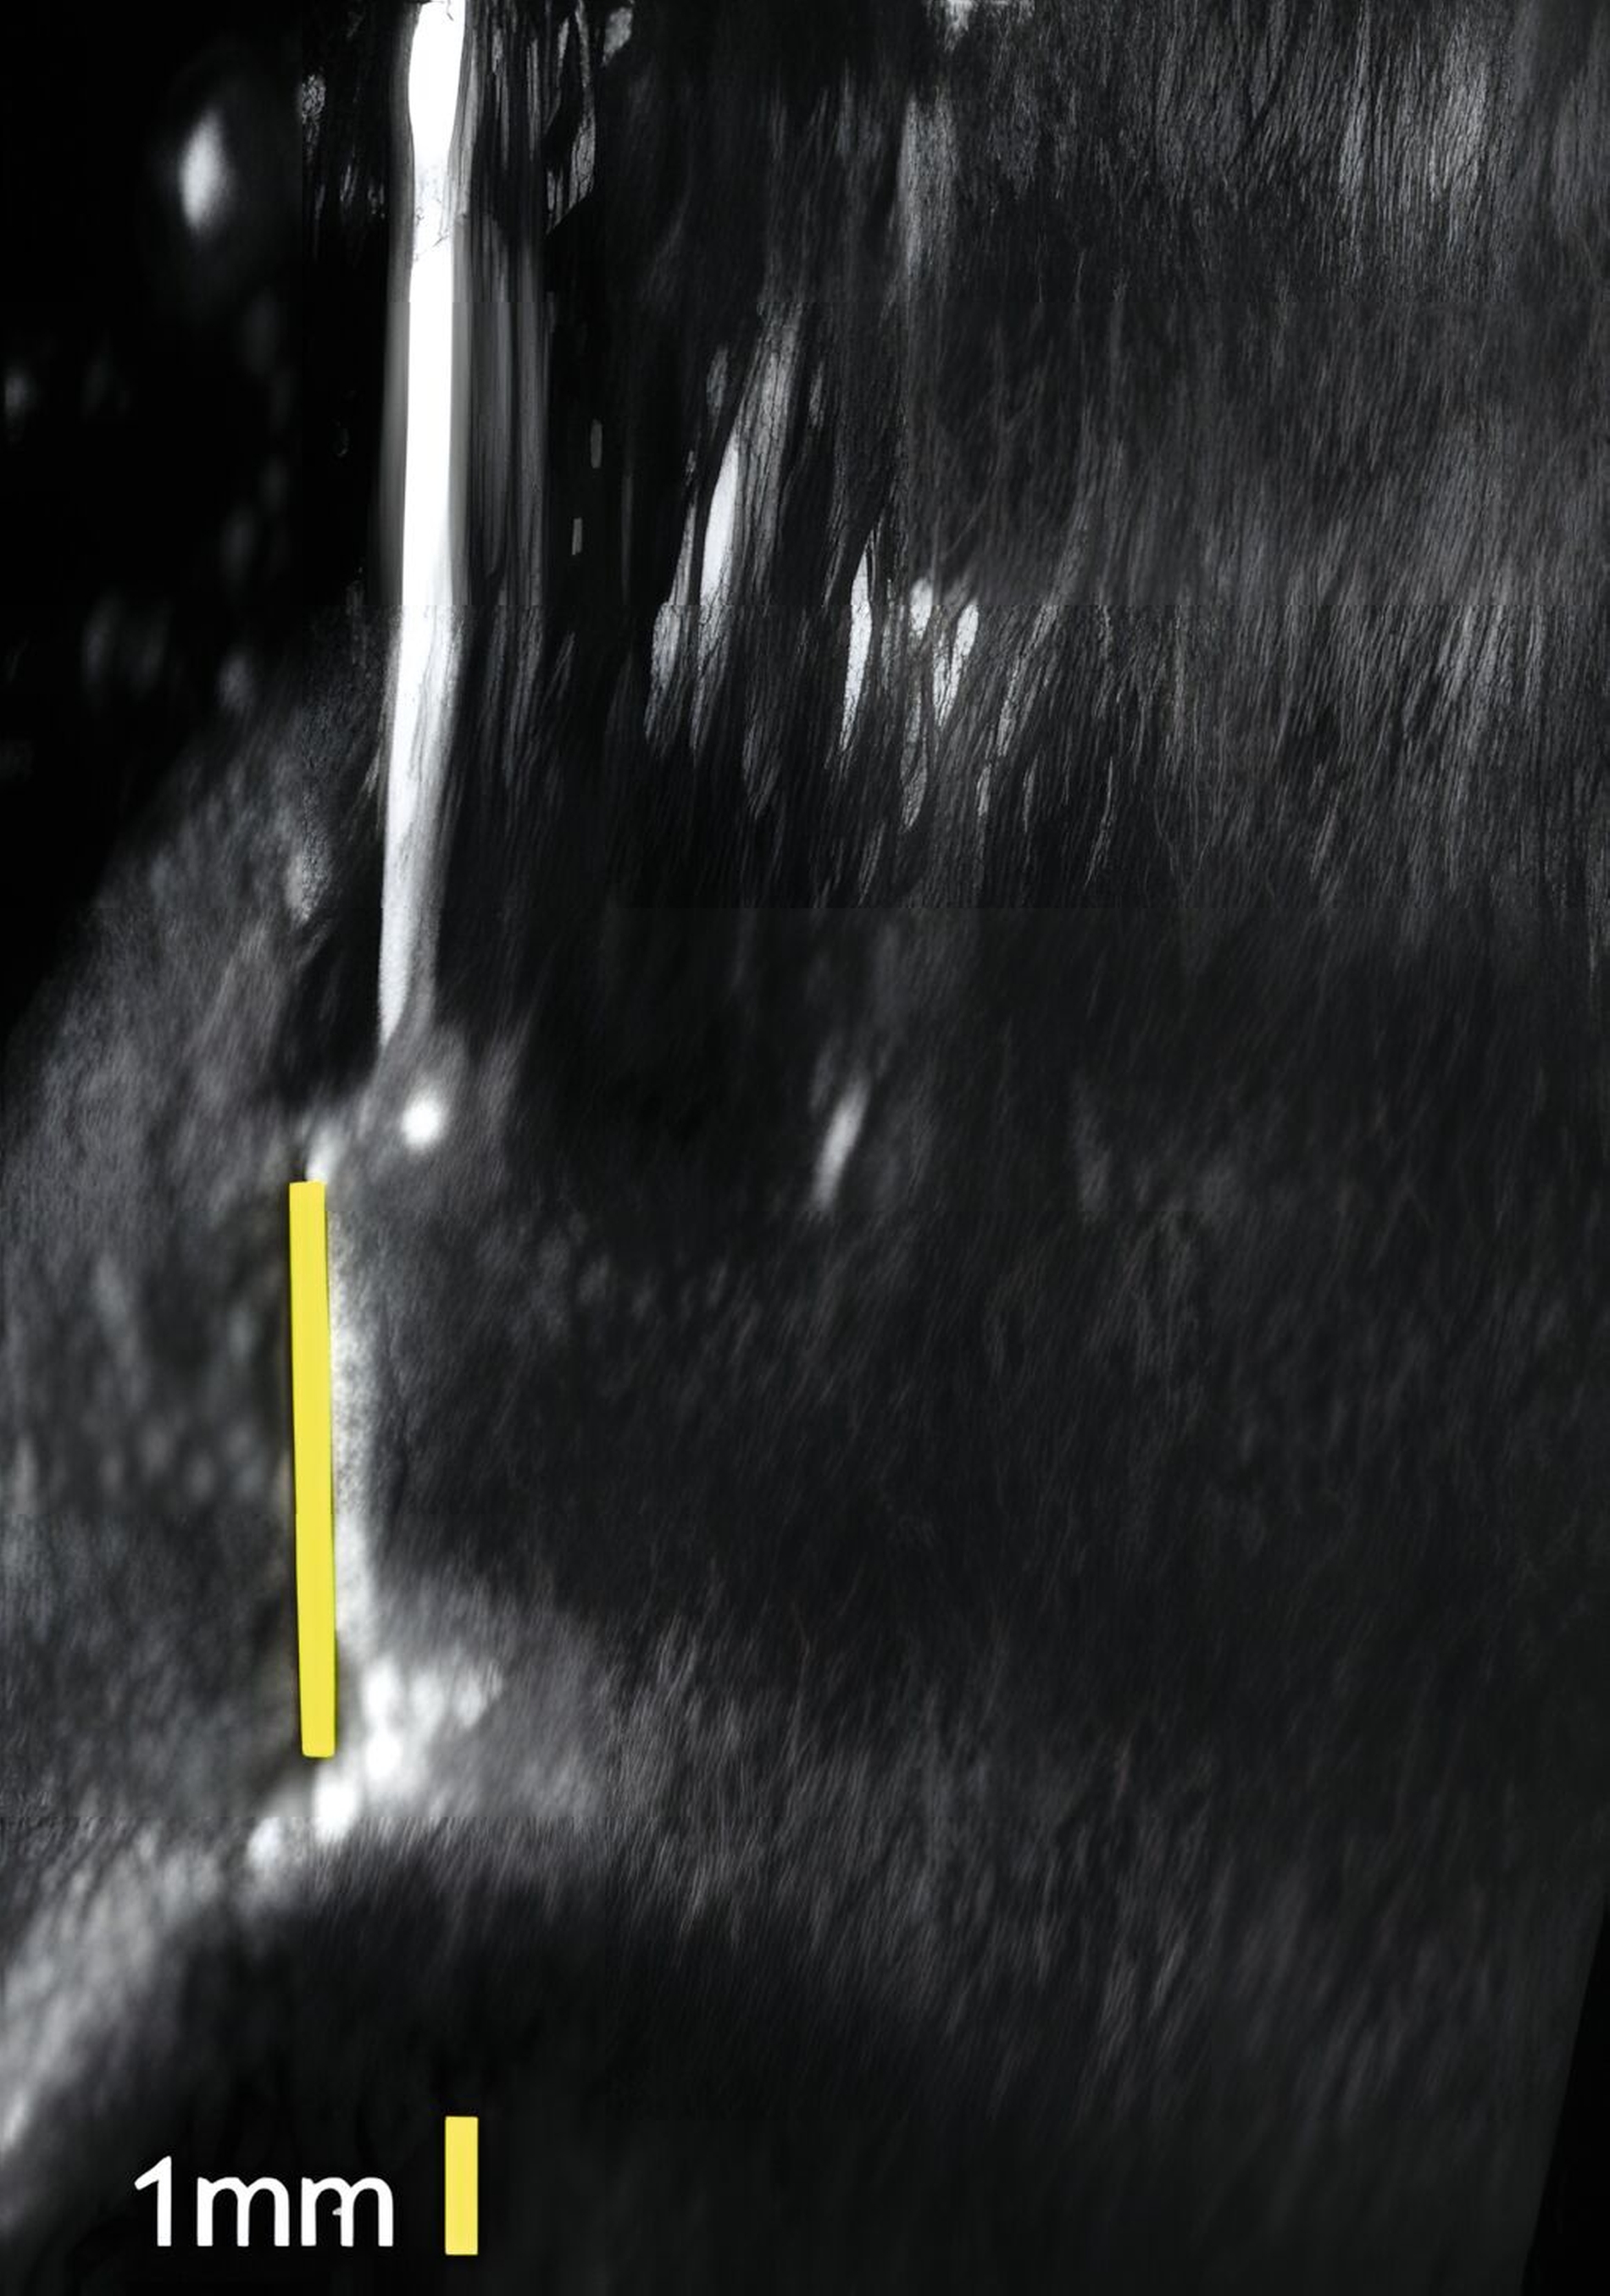

Dies konnte in einer ebenfalls eigenen humanen Kadaverstudie bestätigt werden [Bykhovsky et al., 2024]. Dabei wurden an Implantaten standardisiert Fenestrationen (n = 7), Dehiszenzen (n = 14) und dreiwandige Knochendefekte (n = 6) präpariert (Abbildungen 6 bis 8). Die Defekte wurden mit US- und DVT-Aufnahmen untersucht und die Messungen mit den direkten Messungen verglichen. Die US-Messungen zeigten eine starke Korrelation mit den direkten und den DVT-Messungen. Die sonografische Messgenauigkeit war bei Dehiszenzen am höchsten, gefolgt von Fenestrationen und dreiwandigen Knochendefekten.